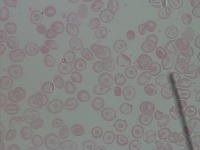

Medical Diagnosis and Research: The "New-Chula" model could be used in medical laboratories and hospitals to automatically identify and classify different cell types in blood samples. This could assist in diagnosing various blood disorders or diseases such as anemia or leukemia, thereby speeding up analysis and treatment processes.

Education and Training: The model could serve as an educational tool for medical students or professionals in training. By using this model, they could learn to identify various types of cells more quickly and accurately, enhancing their understanding of hematology.

Pharmaceutical Trials: During drug testing and development, pharmaceutical companies may use this model to analyze the impact of drugs on different cell types in order to assess effectiveness or side effects.

Public Health Monitoring: Governments and public health organizations could use it to monitor the health condition of the general population, potentially detecting the early stages of an outbreak or epidemic.

Biotechnology Industry: Biotech firms or research labs may use this model for particular research projects involving genetic modification or cellular biology studies where identification and classification of different cell types is necessary.